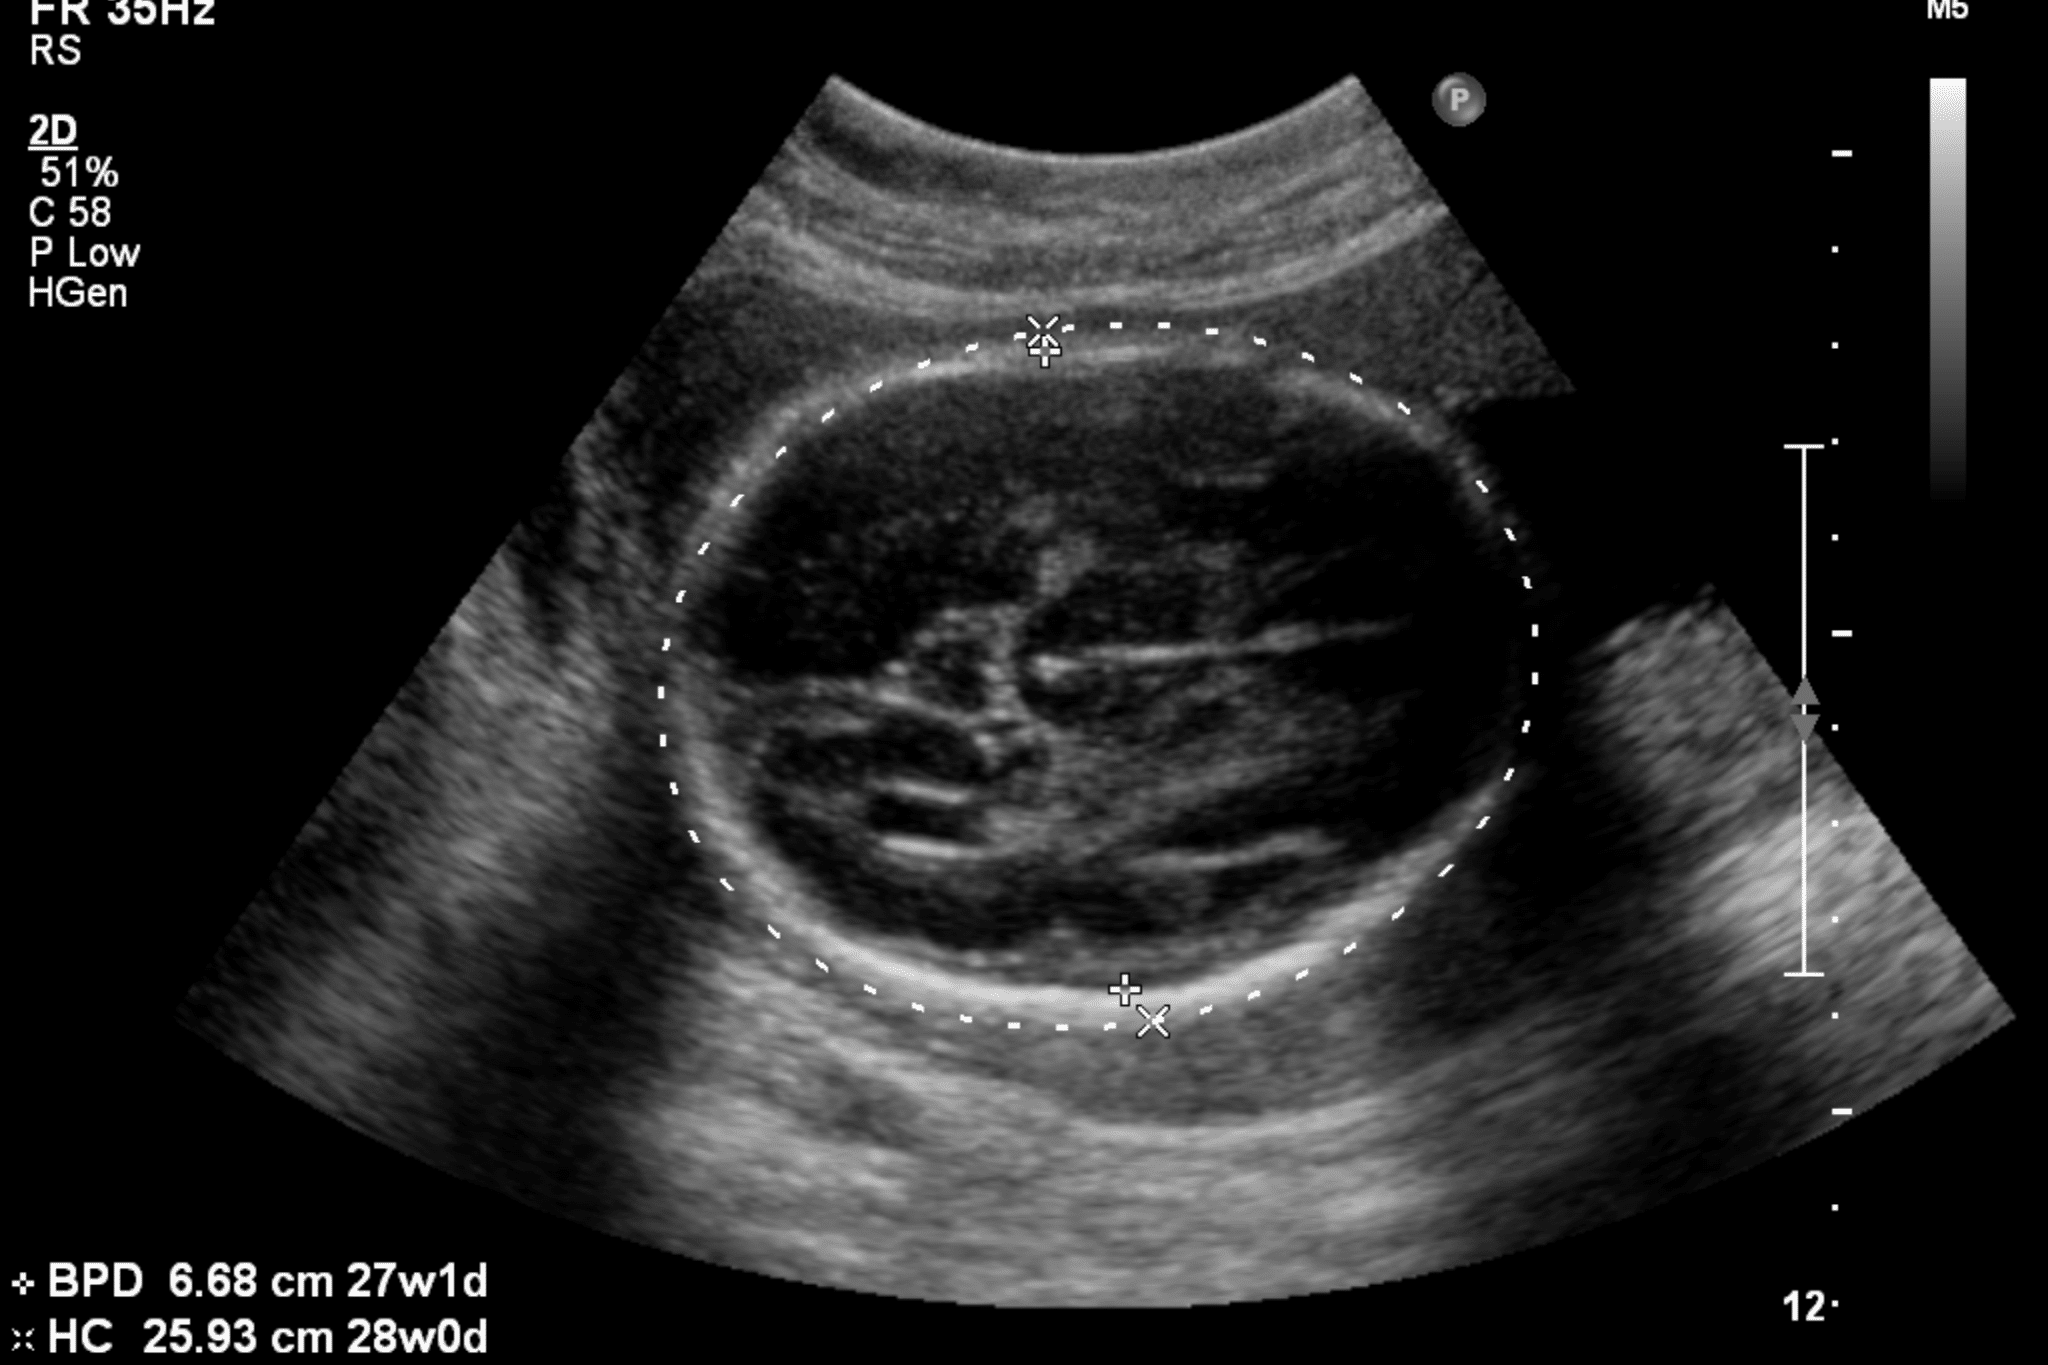

HOW TO CALCULATE GESTATIONAL AGE AND EDD /DUE DATE BY ULTRASOUND DATING SCAN SECOND TRIMESTER Dating Ultrasound Definition It may take you by surprise. Ultrasound between 18 to 20 weeks allows both optimal dating criteria and a detailed anatomical survey of the fetus. Find out when it will happen, what it will be like and what it can tell you. Ultrasound measurement of the embryo or fetus in the first trimester (up to and including 13 6/7 weeks. Dating Ultrasound Definition.